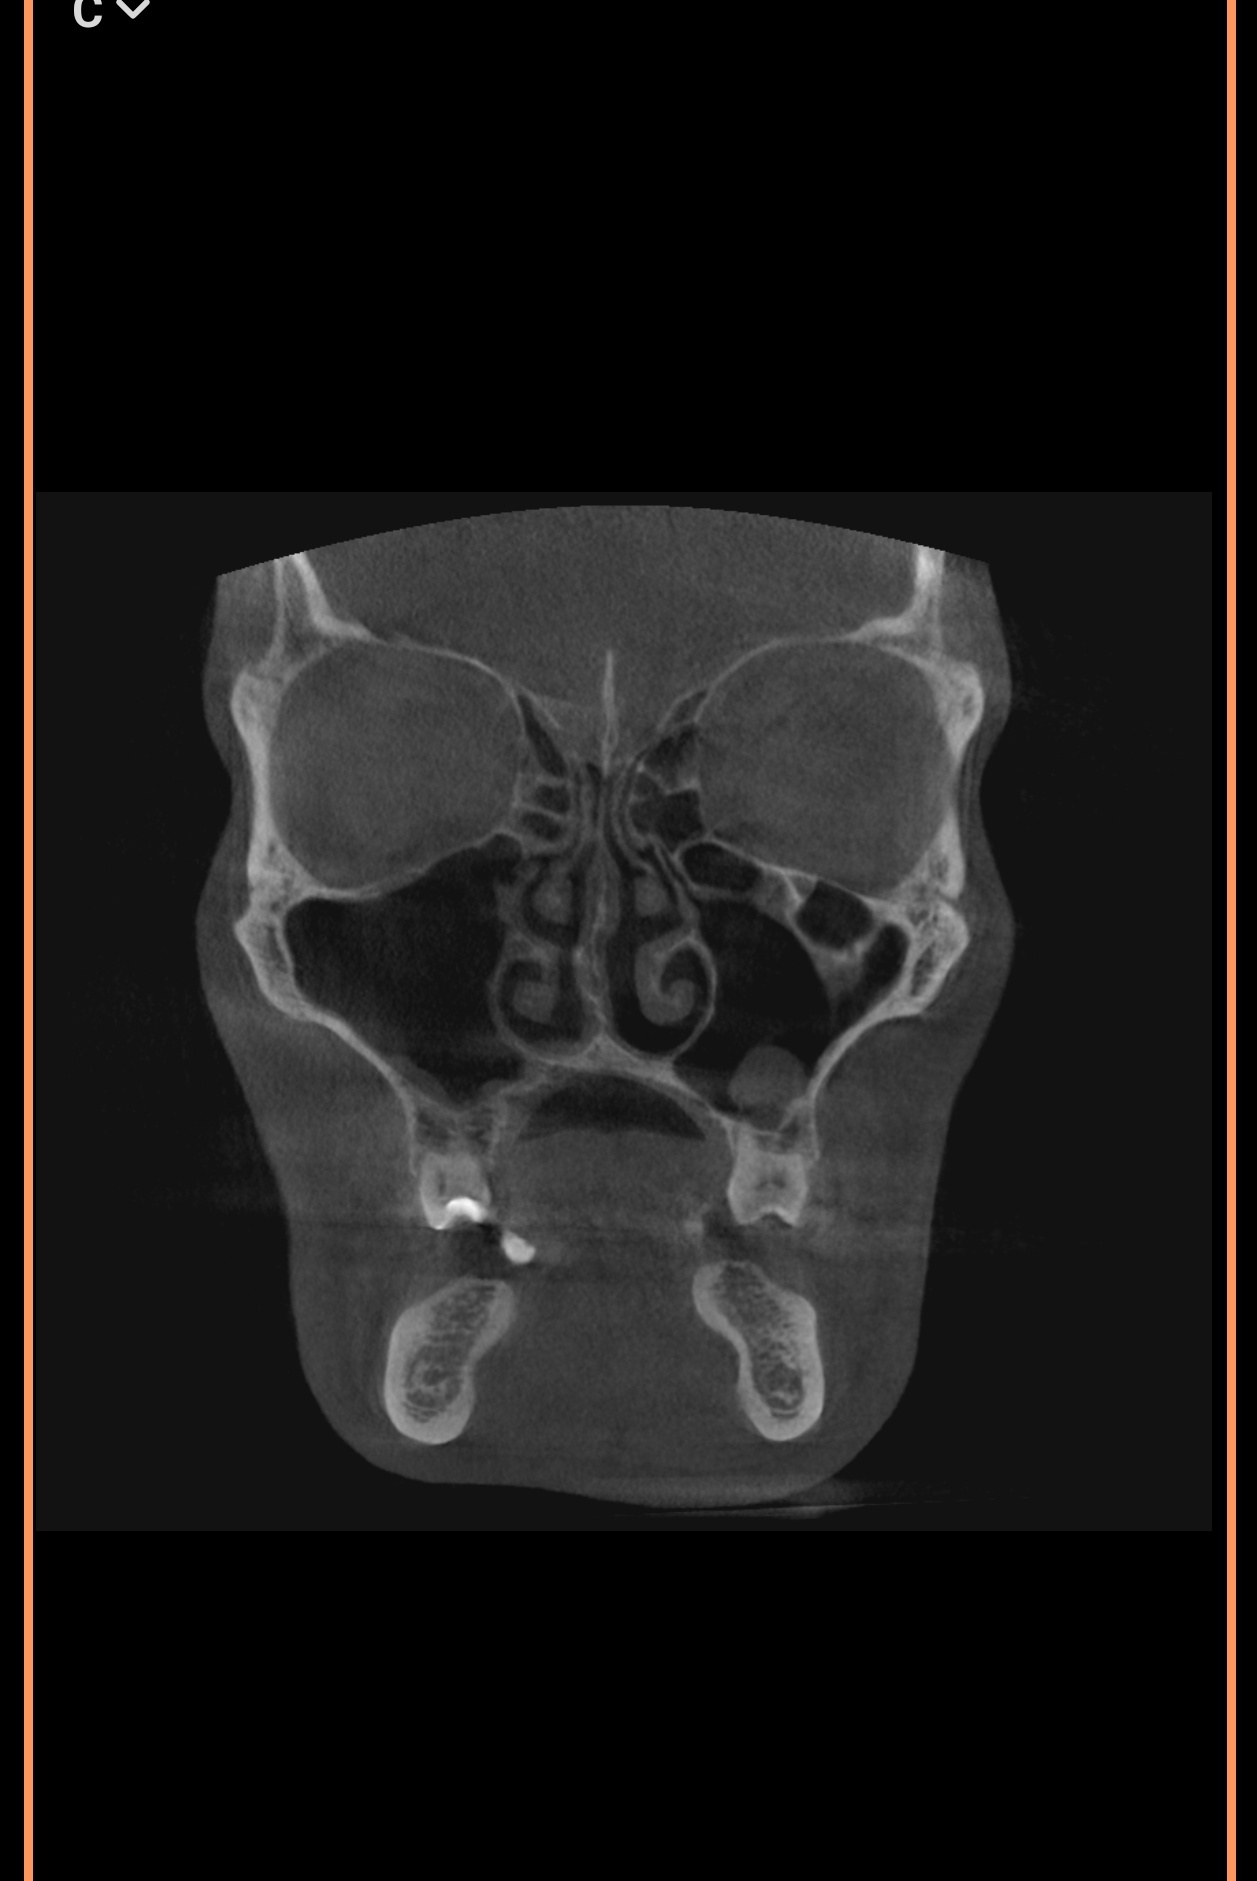

Тут же нужно выпрямлять носовые каналы или как это называется ? А то есть подозрение, что нудно будто бы всегда заложен и я чутка гундошу (когда слышу себя на записи)